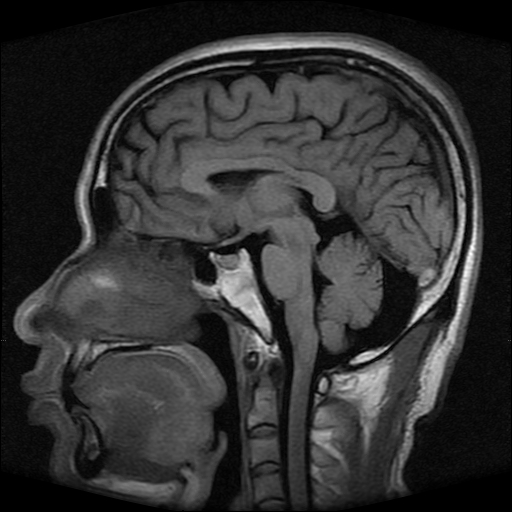

标题: MRI2584:静脉窦血栓?请会诊!

男性,39岁。头晕,视物模糊2月余。血压142/85。矢状窦内高信号有问题吗?

正常脂肪信号影。

正常,若不放心,可以mrv证实

这种病例以前也见过, 但平常的阅片过程比较少注意,而且一些资料上介绍或者图片也比较少,我觉得此病例应该考虑静脉窦血栓。

起码近来我注意的正常人静脉窦内部不是如此信号。

t1wi像可以出现缓慢流速血管呈高信号,应加t2wi及mrv